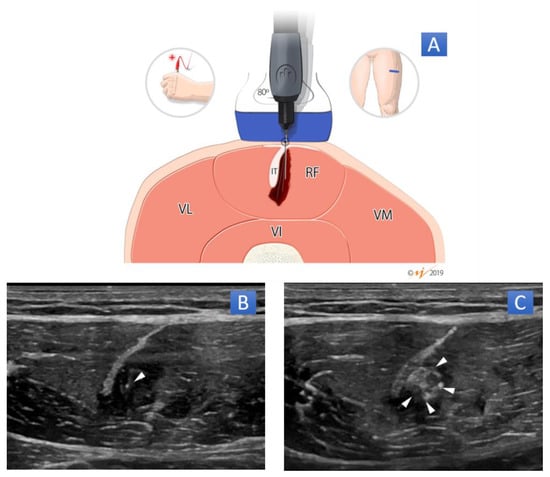

3.1. US-Guided Percutaneous Needle Electrolysis (PNE)